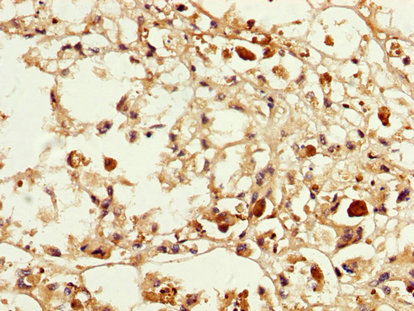

IHC image of CSB-PA013329LA01HU diluted at 1:200 and staining in paraffin-embedded human lung cancer performed on a Leica BondTM system. After dewaxing and hydration, antigen retrieval was mediated by high pressure in a citrate buffer (pH 6.0). Section was blocked with 10% normal goat serum 30min at RT. Then primary antibody (1% BSA) was incubated at 4°C overnight. The primary is detected by a biotinylated secondary antibody and visualized using an HRP conjugated SP system.